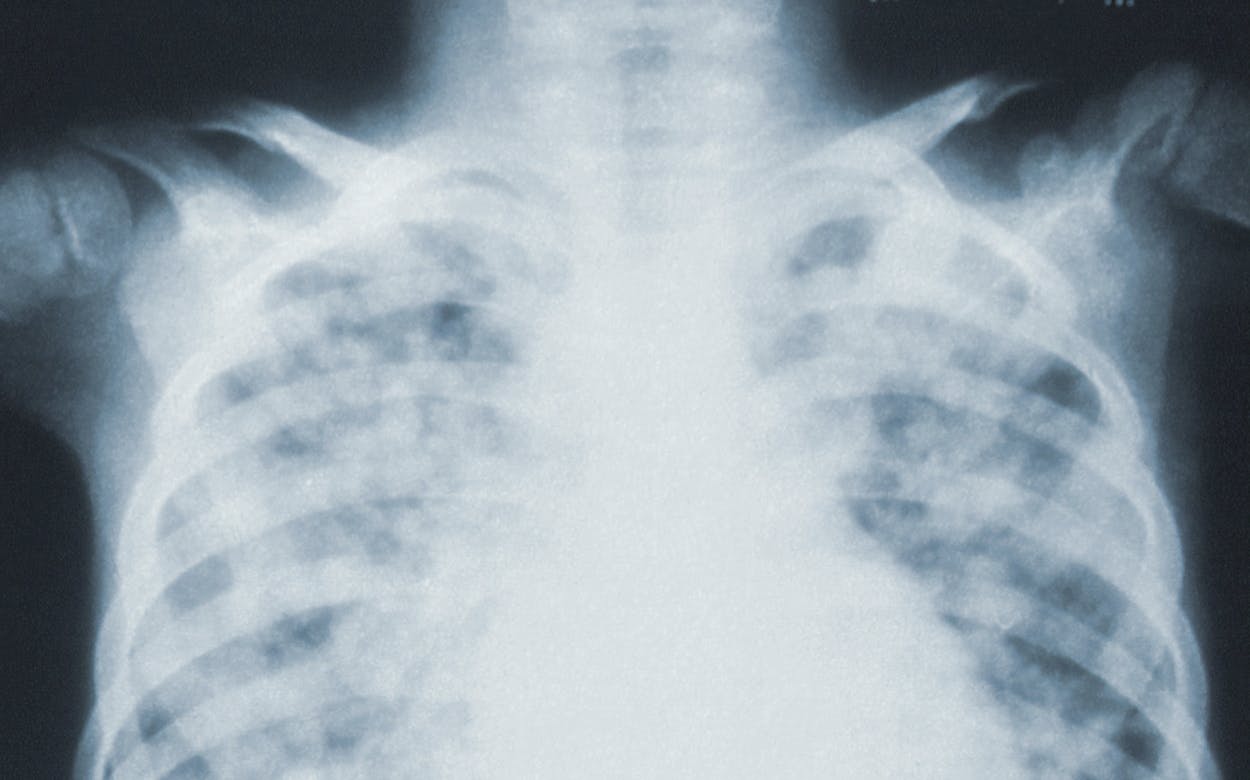

Just a few years ago, most experts agreed that algorithms would dominate radiology until 2021. Medical imaging was considered the predestined field of application for AI, since it involves pattern recognition in large amounts of data.

Fast-forward to 2021, and more than 80 AI algorithms for medical imaging have been approved by the FDA (and a similar number in Europe). However, the reality about these algorithms’ utilization is sobering. Only about 11 percent of radiologists use AI for image interpretation in clinical practice, and 72 percent of those not using AI have no plans to do so. The reason for this slow adoption is poor performance. Only 5.7 percent of users report that AI always works, while 94 percent report inconsistent results.